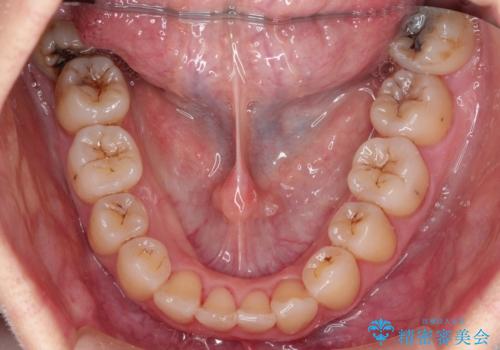

- 審美装置(ブラケット:白/ワイヤー:白)

初診時の歯並びの状態としては、上下ともに前歯部の中等度のがたつきがあり、下の前歯は本来生えるはずの歯が2本生まれつき欠損している状態でした。

抜歯ありワイヤー矯正にて治療を行い、抜歯する歯に関しては虫歯で抜歯が必要な部分を有効活用することで、健康な歯を保存するように努めました。

噛み合わせが深い過蓋咬合という状態でもあったため、下の歯の装置をつけたり、嚙み合わせを上げる(下の歯が見える状態にする)ことにたいへんに苦労した症例でした。

見た目、嚙み合わせ及び、治療期間や施術内容に大変ご満足いただきました。